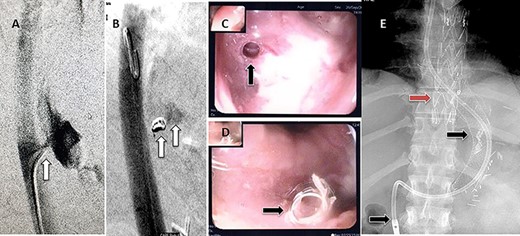

(A) Aortography showed active contrast extravasation to the esophagus trough the fistula. (B) Coli embolization of the AEF with contrast beyond the coil. (C) Esophagogastroduodenoscopy revealed the site of the fistula and the coil embolization in the stomach. (D) An esophageal stent was placed extending to the stomach and the aortic stent in place. Feeding tube in place.